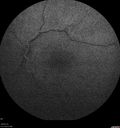

Chronic Endophthalmitis and Cystoid Macular Edema436 viewsVA 20/50 - Culture negative. Cleared with intravitreal antibiotics and decadron00000

Chronic Endophthalmitis and Cystoid Macular Edema390 viewsVA 20/50 - Culture negative. Cleared with intravitreal antibiotics and decadron00000

Chronic Endophthalmitis and Cystoid Macular Edema414 viewsVA 20/50 - Culture negative. Cleared with intravitreal antibiotics and decadron00000

Chronic Endophthalmitis and Cystoid Macular Edema402 viewsVA 20/50 - Culture negative. Cleared with intravitreal antibiotics and decadron00000